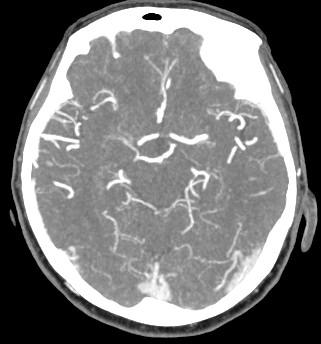

Мультиспиральная компьютерная томография головного мозга относится к лучевым методам исследования и основана на использовании проникающей способности рентгеновских лучей, которые в различной степени поглощаются органами и тканями. Степень поглощения зависит от плотности анатомических структур, благодаря чему можно получить подробные изображения внутренних органов. Во время исследования трубка томографа вращается вокруг пациента и производит снимки поперечного сечения, что позволяет детально визуализировать кости черепа и все структуры головного мозга.

Для улучшения видимости внутричерепных структур применяется методика внутривенного болюсного контрастирования. Во время проведения КТ пациенту в вену вводится йодсодержащее контрастное вещество. Контраст с током крови попадает в патологически измененные участки ткани и очаги, что на снимках придает им яркие отличительные признаки по сравнению с окружающими здоровыми тканями. Контрастирование, в первую очередь, помогает в диагностике опухолевых процессов на ранних стадиях, когда лечение может дать наилучший результат.

В наших медицинских центрах КТ головного мозга с контрастированием проводится на новейших мультиспиральных компьютерных томографах экспертного уровня TOSHIBA AQUILION в различных модификациях. Аппараты снабжены увеличенным количеством сверхчувствительных детекторов, что позволяет при сканировании выполнять множество срезов поперечного сечения с минимальной толщиной среза от 0,5 мм. В результате получаются изображения исследуемой зоны в мельчайших подробностях, которые затем с помощью инновационных цифровых приложений преобразуются в трехмерные пространственные модели головного мозга для более точной диагностики. Помимо высокого качества изображений увеличенное количество детекторов обеспечивает быстроту выполнения сканирования, что значительно снижает уровень рентгеновского облучения для пациента во время обследования.